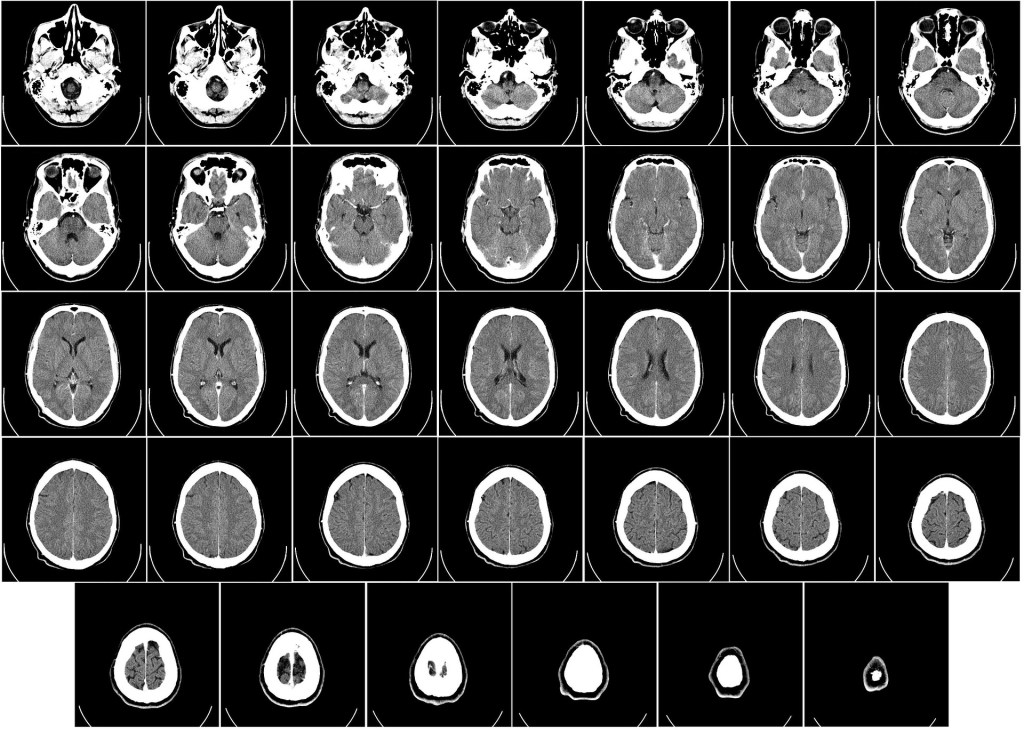

Injury in the brain, following stroke for example, really only differs in that brain tissue, once truly lost doesn’t regrow in the same way other tissues grow, if it regrows at all. There are however those cases where brain tissue is not completely lost but rather rendered ischaemic following a hypoxic episode. And that really is all it is, an hypoxic episode caused by a blockage or other vascular failing. This is the tissue that can potentially be rejuvenated by improving oxygen transport to those cells affected. Granted, HBOT won’t necessarily benefit ALL stroke patients since we can’t know to what extent tissue is necrotic or ischaemic. In cases of stroke, patients often report loss of eyesight on one side or the other. This too can result from ischaemia and doesn’t necessarily indicate necrotic cells and tissue. SPECT imaging can show up areas of necrotic tissue and those areas which are ischaemic by highlighting blood flow in the brain. Please note that necrotic tissue cannot be rejuvenated. Oxygen can only act on cells which haven’t yet become necrotic. Salvaging ischaemic tissue in conjunction with newly established evidence of continued nueroplasticity throughout life gives cause for hope. By salvaging what is possible to savage, in conjunction with other therapies, brain function, through continued plasticity, can potentially develop new pathways through which to function.